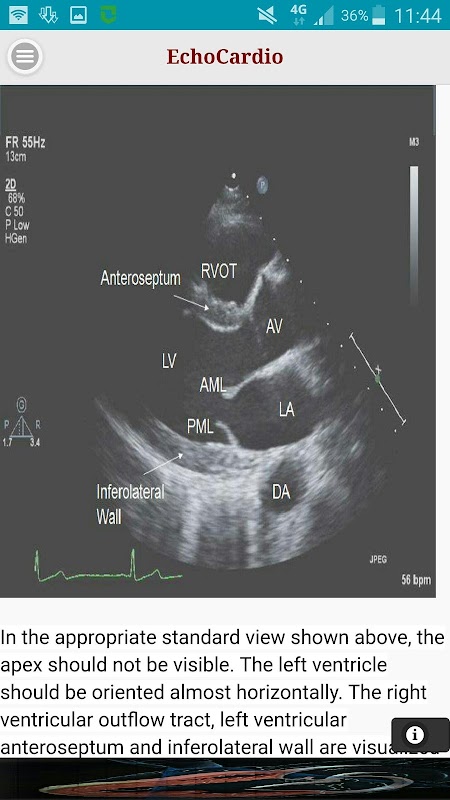

Parasternal Long Axis